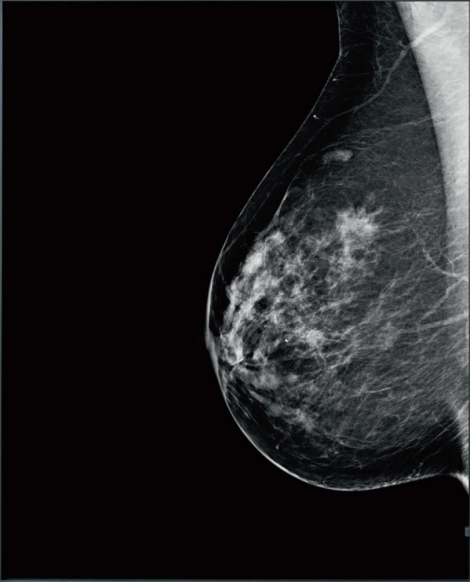

| GM550是一款21.3英寸高亮度诊断医疗显示器,500万像素像素(分辨率2048X2560)、0.165的点距满足乳腺诊断标准。 | ![]() |

| +8MP.MC850 | 高分辨率 本诊断显示器具备超高的分辨率,21.3寸的屏幕显示500万像素(2560X2048)的信息,0.165的点距能够让您清晰查看数字乳腺X线摄影中至关重要的微小细节。高分辨率可保留重要信息,以防在较低分辨率下查看图像时图像质量和像素的下降。 超高亮度 显示器原生面板具备1200cd/m2的超高对比度,医疗图像中明暗区域最亮的白和最暗的黑之间不同亮度层级更容易生动的显示出来,更能准确的显示各阶的颜色。5MP的分辨率更让细微的乳腺钙化点得以呈现出来。 高灰阶度 显示器具备48BIT(R\G\B)查找表,可以同步显示10位色彩,10BIT灰阶可以让画面过度更加的平滑,保证高端影像设备采集的高灰阶影像能完整的呈现在医生眼前,平滑的灰阶过渡更利于医生发现正常组织和病灶组织的差异。 查看胶片的观片灯 为了便于观看胶片,显示器内置了观片灯功能,可以一键开启单屏、全屏模式,方便医生读取胶片。 预设多组DICOM标准曲线 显示器完全符合DICOM Part 3.14部分的关于医用诊断显示器的标准,内置多组医疗影像标准曲线,如伽玛1.8-2.4,DICOM1\DICOM2\DSA等。 显示器前端触摸式按钮 采用触摸式按钮,便于用户便捷的启用快捷功能,如开启关闭灯箱. 出厂的精准调试 每一台显示器在出厂前,均进行多个灰阶色调的测量,使显示器更符合DICOM Part 14的标准,确保灰阶过渡的平滑一致性,更利于精确的诊断。全屏幕25个点进行亮度和色度测量,进行屏幕均匀性调试,确保全屏幕均匀一致的亮度和色度效果。确保曲线误差值 和屏幕均匀性(Delta E)在<= 5( avg)。 亮度恒定输出保障 内置背光传感器,实时探测屏幕亮度的变化,并进行实时准确性修正,确保显示器亮度保持长期稳定性、一致性。 环境光感应技术 屏幕前端具有环境光感应器,开启后可以感应周边环境光线变化,并根据亮度变化自动调节显示器背光亮度,实现保护视力的效果。 多款实用性软件配合诊断工作 可以快速调节多个显示器的亮度控制技术,多屏幕下快速定位鼠标所在位置,多屏幕下不同分辨率显示器使用鼠标平滑无障碍移动软件,局部提高对比度和亮度聚焦浏览,自定义时间或者根据昼夜自动启用功能护眼设置,自动调整亮度和色温等实用软件。 保修 提供长达5年的保修服务。